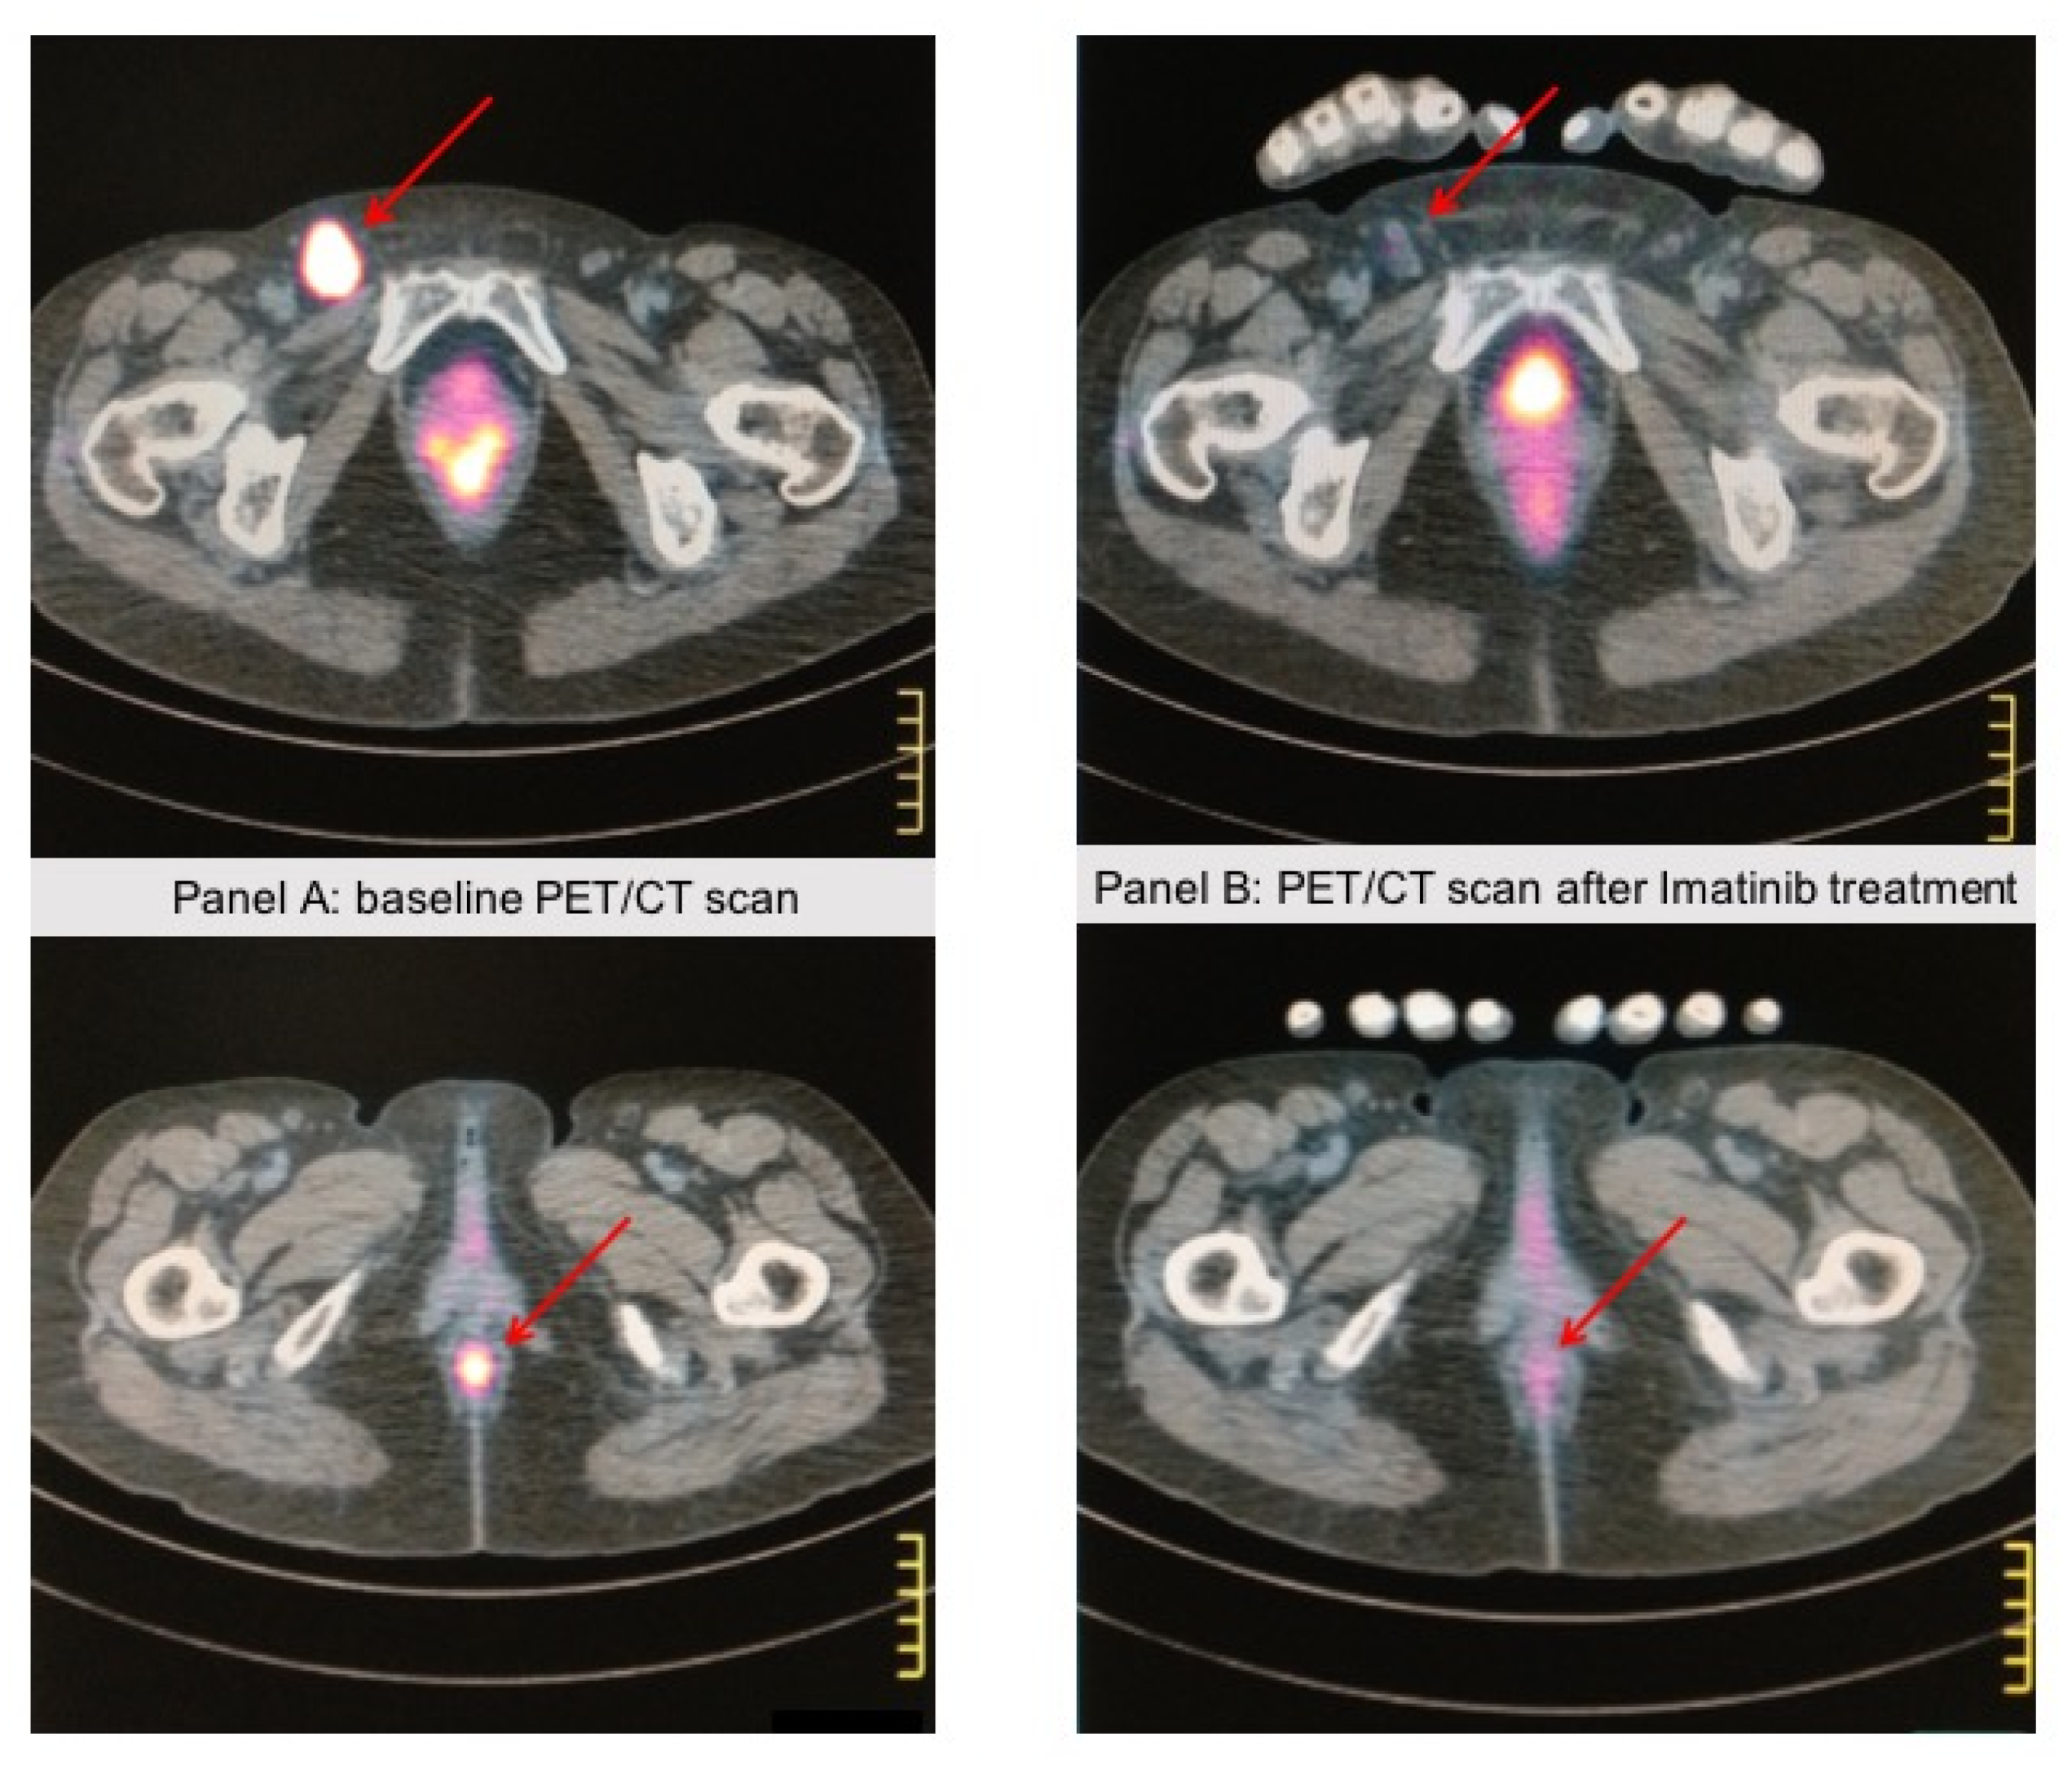

- Carvajal, R.D.; Antonescu, C.R.; Wolchok, J.D.; Chapman, P.B.; Roman, R.A.; Teitcher, J.; Panageas, K.S.; Busam, K.J.; Chmielowski, B.; Lutzky, J.; et al. KIT as a therapeutic target in metastatic melanoma. JAMA 2011, 305, 2327–2334. [Google Scholar] [CrossRef] [PubMed] [Green Version]

- Hodi, F.S.; Corless, C.L.; Giobbie-Hurder, A.; Fletcher, J.A.; Zhu, M.; Marino-Enriquez, A.; Friedlander, P.; Gonzalez, R.; Weber, J.S.; Gajewski, T.F.; et al. Imatinib for melanomas harboring mutationally activated or amplified KIT arising on mucosal, acral, and chronically sun-damaged skin. J. Clin. Oncol. 2013, 31, 3182–3190. [Google Scholar] [CrossRef] [Green Version]

- Steeb, T.; Wessely, A.; Petzold, A.; Kohl, C.; Erdmann, M.; Berking, C.; Heppt, M.V. c-Kit inhibitors for unresectable or metastatic mucosal, acral or chronically sun-damaged melanoma: A systematic review and one-arm meta-analysis. Eur. J. Cancer 2021, 157, 348–357. [Google Scholar] [CrossRef]